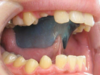

L' ENVELOPPE LINGUALE NOCTURNE (ELN)

L' Enveloppe Linguale Nocturne ou ELN est un appareil de rééducation de la langue.

Son but est de corriger la position de la langue au repos et pendant la déglutition

afin de l’empêcher de s'interposer entre les dents.